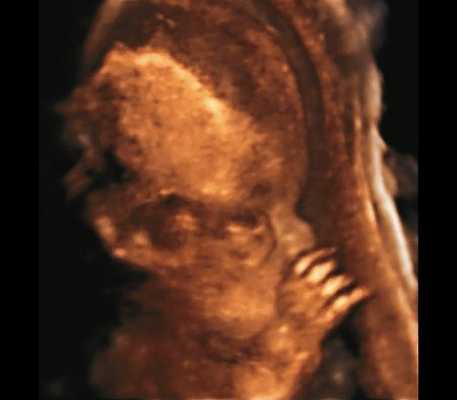

б) Объемная реконструкция. Видны высокий выпуклый лоб, расширенный передний родничок и сагиттальный шов, правильная установка пальцев.

| Набл. 4. 26,5 нед? | БПР - 22,6 нед. ОГ - 22,6 нед. Форма - трилистник (рис. 4а). Боковые желудочки - 22 мм, высокий лоб, расширенный родничок, сагиттальный шов (рис. 4б). | Торакоабдоминальное соотношение - 65,7% (рис. 4в). Окружность груди - среднее для 23 нед. Колоколообразная форма. | ДБ - 23 мм (51% от должной). Остальные кости - 50% для 15-17 нед. Нормальная установка пальцев кисти (рис. 4б). | Уплощенные тела поясничных позвонков (рис. 4г). |

Так, в наблюдении 4 наряду с узкой грудной клеткой и микромелией наличие типичной формы головы в виде трилистника у плода позволило без трудностей установить диагноз ТД II типа.